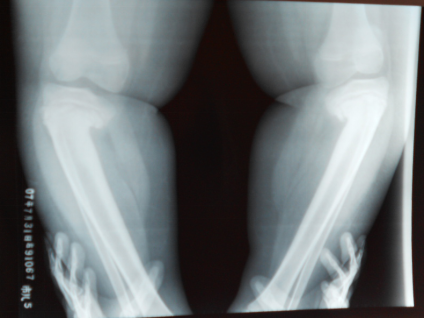

√ 骨骼

√ 股骨骨骺异常